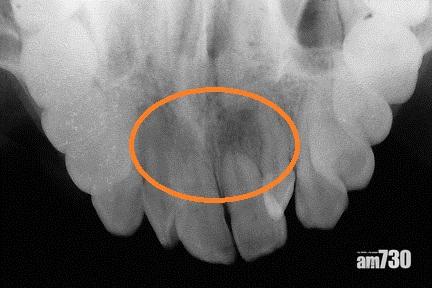

矯齒治療前

矯齒治療後門牙有牙腳收縮現象(此為嚴重收縮病例)。